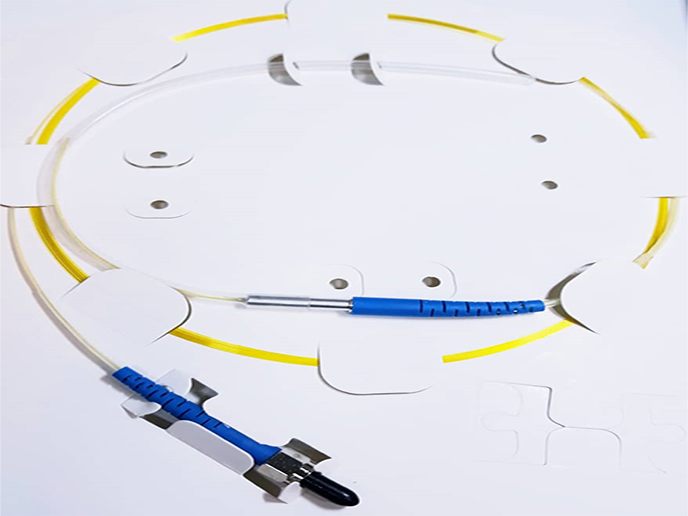

Disposable Polyimide Coated Single ring Radial Fiber

A single ring 400um to 600 um shaped fiber guarantee very high mechanical stability and excellent beam quality.

Properties |

Fiber type Loose Tube |

400 and 600um Colored Hytrel or without loose tube |

|

Fiber length |

2m |

|

Connector type |

SMA905 connector or HP-SMA905 |

|

Distal tip NA Sterilization |

Encapsulated angled tip 0.22 EtO-sterilized |

Application

Vascular, plastic, gynecological and ENT surgery

Hemorrhoids and fistulas, Endo-Lift.

Optional features

- extension sleeve available in various colors

- Laser inscription possible

- Customer-optimized designs on request

- Various accessories available

Clinical Tests has done by a group of specialized in diseases and laser surgery of the hemorrhoids and fistulas . (Iran, Nov. 2021). Results has been satisfactory on more than 40s patients.

Certifications & approvals: (In Progress)

Our production processes, devices and procedures is certified by ISO 13485 .

And Iran national medical device directorate (IMED)